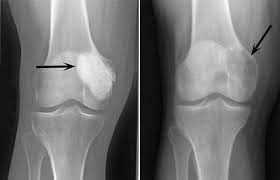

Остеобластома имеет схожие симптомы с другими опухолями костей, поэтому для ее выявления требуется провести комплексную диагностику, от которой будет зависеть выбор лечебных мер. Обнаружить образование помогает рентгенологическое обследование, которым диагностика не ограничивается, поскольку нужно предварительный диагноз подтвердить, определить размер остеобластомы и границы поражения. Поэтому обычно пациенту назначают инструментальные способы исследования, сканирование костей. По результатам диагностики подбирается схема лечения: